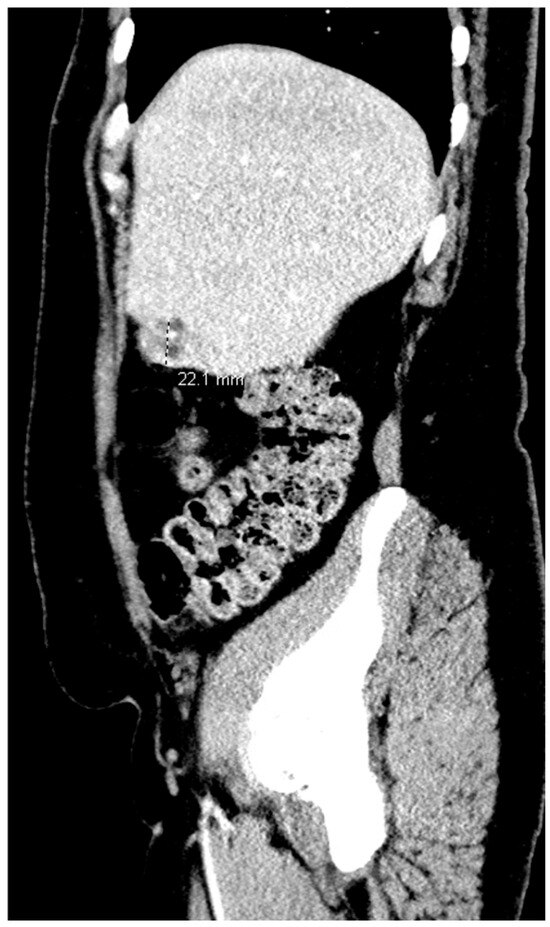

Pregnancy (HP), defined as the coexistence of intrauterine and ectopic gestations, is a rare condition, especially in spontaneous conception, but it is a life-threatening obstetric emergency when rupture occurs, with a reported maternal mortality rate of 0.03%. Diagnosis is often delayed because confirmation of an intrauterine pregnancy can mask clinical signs of a concurrent ectopic gestation. Early recognition and prompt surgical intervention are therefore critical to maternal safety and preservation of intrauterine viability. This case highlights the diagnostic challenges and successful management of a spontaneous ruptured heterotopic pregnancy. Case presentation: A 34-year-old Middle Eastern woman, gravida 4, with a spontaneous conception, presented with sudden severe lower abdominal pain and signs of acute hemoperitoneum (hypotension, tachycardia, and marked peritoneal signs). Transvaginal ultrasound demonstrated a viable intrauterine pregnancy at 9 weeks 4 days gestation, together with a ruptured left tubal ectopic pregnancy of similar gestational age. The patient underwent urgent laparoscopic left salpingectomy with evacuation of approximately 1200 mL of intraperitoneal blood and clots. Postoperatively, she developed significant anemia (hemoglobin drop from 11.2 g/dL on admission to 6.5 g/dL) requiring transfusion of four units of packed red blood cells. Serial ultrasonographic follow-up confirmed ongoing viability of the intrauterine pregnancy, which ultimately resulted in a live birth at term. Progressive resolution of the postoperative pelvic hematoma was also noted. Conclusions: Ruptured heterotopic pregnancy remains a diagnostic and therapeutic challenge. This case, along with a synthesis of the contemporary literature, demonstrates that a high clinical index of suspicion, timely ultrasound diagnosis, and immediate minimally invasive surgical management are paramount. Furthermore, rigorous postoperative monitoring and resuscitation, including targeted transfusion, are essential to achieve maternal stabilization while allowing continuation of a viable intrauterine pregnancy, with reported live birth rates exceeding 70% following timely intervention. Full article